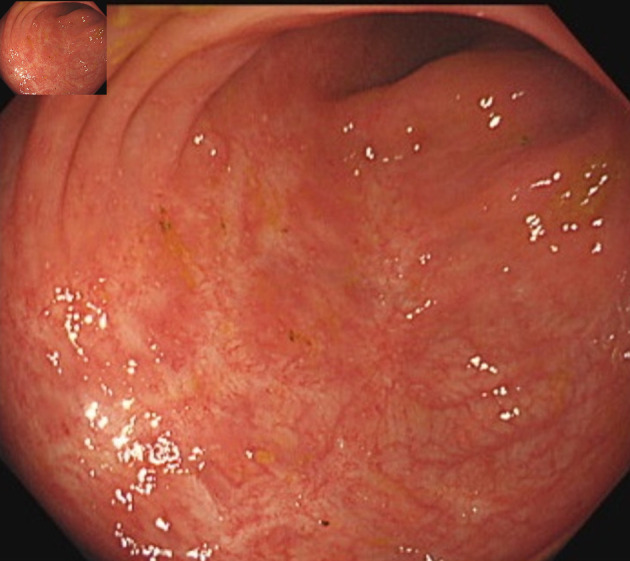

A 23-year-old man was diagnosed with Crohn's disease (CD) of the large intestine after colonoscopy revealed longitudinal ulcers, and pathology revealed non-caseating epithelioid cell granulomas and anal fistulas. The CD relapsed, and therefore prednisolone (PSL) and infliximab (IFX) treatment was initiated. The PSL was gradually tapered. Steroid-free remission was maintained with IFX. The patient subsequently developed a high fever and headache, while CD-related symptoms did not worsen. Laboratory data showed white blood cells at 14,200/µL and C-reactive protein at 17.2 mg/dL. Contrast-enhanced computed tomography revealed thoracoabdominal aortitis, and the patient was consequently diagnosed with Takayasu's arteritis (TA). We therefore again initiated PSL treatment that immediately reduced the fever and headache. The PSL dose was again tapered and the administration of IFX was resumed to maintain CD remission. No further episodes of aortitis relapse were noted after restarting IFX, and the CD currently remains in remission. This is a rare case of TA onset during IFX treatment for CD, and, as such, contributes to the limited literature on such cases. More specifically, this case highlights that when patients with CD present with symptoms such as fever or headache, it is necessary to investigate the possibility of vasculitis.

Abstract Image